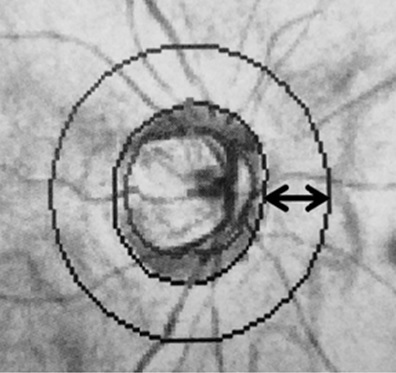

Background: Associations between retinal venous occlusion (RVO), elevated intraocular pressure, and glaucoma have been reported. Further investigations into structural alterations in the fellow eyes of individuals with unilateral RVO have revealed that the peripapillary retinal nerve fiber layer is thinner than in healthy eyes, suggesting that there may be systemic risk factors common to both RVO and glaucoma. We aimed to evaluate changes in peripapillary retinal nerve fiber layer thickness (pRNFLT) among individuals with unilateral branch retinal vein occlusion (BRVO).

Methods: This prospective observational study recruited 30 individuals (60 eyes) with newly diagnosed unilateral BRVO and macular edema, and a control group of 30 healthy individuals (30 eyes) with no abnormalities on fundus examination or concurrent systemic comorbidities. After baseline measurements, the participants were reassessed at 6, 12, and 24 months by measuring global and sectoral pRNFLT using spectral-domain optical coherence tomography.

Results: The mean age and sex distributions were comparable between the patient and control groups (both P > 0.05). When compared to fellow eyes, global and sectoral pRNFLT in eyes with BRVO were significantly higher at baseline (all P < 0.05). Over time, pRNFLT decreased dramatically, and by the conclusion of the two-year follow-up, there was a significant reduction from baseline in the affected eyes (all P < 0.05). Likewise, affected eyes experienced a significant improvement in best-corrected distance visual acuity and central macular thickness over the two-year follow-up (both P Less than or equal to 0.001). Comparing the global and all-sector pRNFLT of fellow eyes in the patient group with those of normal eyes in the control group, there were no significant differences at any visit, except in the temporal sector, which revealed a significant reduction in pRNFLT at 24 months in the fellow eyes of patients with unilateral BRVO (P = 0.02).

Conclusions: Patients with unilateral BRVO experienced a significant reduction in pRNFLT in the affected eyes and, to a lesser extent, in the fellow eyes, compared with that of the control arm, suggesting that they are prone to retinal nerve fiber layer damage. The reduction in pRNFLT in the normal fellow eyes of patients with BRVO may be attributed to age or concurrent systemic comorbidities. Further studies with long follow-up periods are required to shed light on the etiology of functional and structural changes in both the retinal nerve fiber layer and ganglion cell complex in the normal and affected eyes of patients with unilateral BRVO.